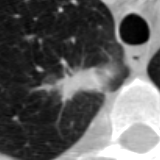

The current study focuses on lung nodule retrieval from a database of CT scans, where patches taken from CT slices of pulmonary nodules are to be mapped into an embedding. LIDC-IDRI [5] is a dataset of thoracic CT scans of 1,010 patients. All the scans were annotated by up to four radiologists, where each one identified, segmented and evaluated separately the lung nodules of a diameter above . Their evaluation also included ratings for a set of 9 characteristics: Subtlety, Internal structure, Calcification, Sphericity, Margin, Lobulation, Spiculation, Texture and Malignancy. The rating system was based on a discrete score of 1-5. Four examples of nodule patches are illustrated in Figure 2: 2 benign (a, b) and 2 malignant (c, d). A rounded vector of the mean rating is bellow each nodule, with the characteristics ordered according to the listing above. The most prominent difference between a and b is the calcification: 3 (solid) and 6 (absent) accordingly. d compared to c has a more defined margin, is more lobulated, but less spiculated. The malignancy score is used to define malignancy classes: score of 1-2 is benign, score of 3 is unknown, and a score of 4-5 is malignant.

(a) Benign

3, 1, 3, 3, 4, 3, 1, 5, 1

(b) Benign

3, 1, 6, 5, 5, 1, 1, 5, 2

(c) Malignant

5, 1, 6, 3, 3, 4, 1, 5, 5

(d) Malignant

4, 1, 6, 3, 4, 2, 2, 5, 4